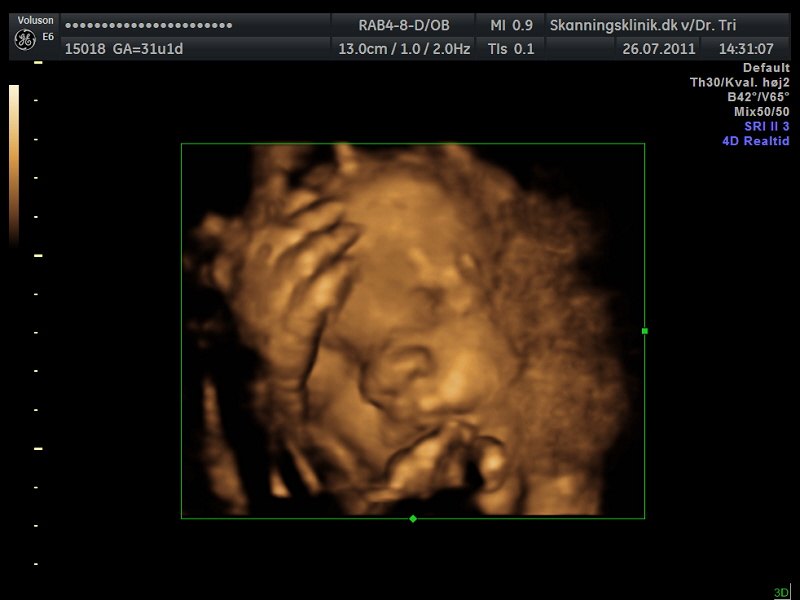

Så blev det tid til en lille 3D/4D-scanning af bettemanden!!

Jeg er i dag 31+2 og var i eftermiddags til 3D/4D-scanning, på skanningsklinikken i Hvidovre, og sikke en oplevelse, helt sikkert alle pengene værd!!

Lillemanden var dog noget svær at få gode billeder af, da han havde skruet numsen ned i mit bækken og synes han skulle ligge med begge hænder og fødder direkte foran hans lille nuttede ansigt hehe.. Så mor her måtte op at hoppe flere gange og fik koldt vand og måtte have maven gennem-rystet flere gange, men alligevel var han nooget på tværs hehe.. Den lille bølle..

Men der kom dog til sidst nogle helt okay billeder ud af det!!

Og så liige lidt billeder, så I også kan se min fine guldklump...

Som I kan se er der lidt hånd og fod med på alle billederne, og på det sidste billede har bettemanden fat om foden med den ene hånd.. Lille hypermobile skid..